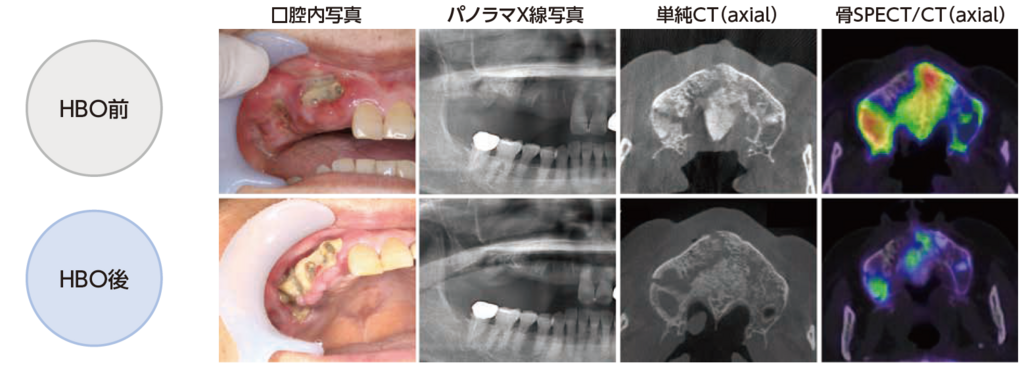

HBO15回施行前後:各所見の比較

単純CT画像は、腐骨の分離状態を確認することはできるが、骨SPECT/CT画像では、腐骨の範囲のみならず炎症波及の程度が確認できることから、HBOの治療効果をより視覚的に判定することができる。

HBO(高気圧酸素療法)前後:GI-BONE 解析結果画像

骨SPECT画像において、MRONJが発症している部位を含んだ範囲をVOIに設定することで、GI-BONE(骨SPECT定量解析ソフトウェア)がVOI内の集積に対するSUVを自動的に算出する。

HBO(高気圧酸素療法 15回施行)前後:GI-BONE 解析結果画像

GI-BONEの定量解析で評価される、5つの項目全ての値がHBO後に下がっていた。

治療前後で骨SPECT/CT画像を撮像し、GI-BONEによる定量評価を実施することで、治療の効果ならびに病態を客観的に評価することができた。